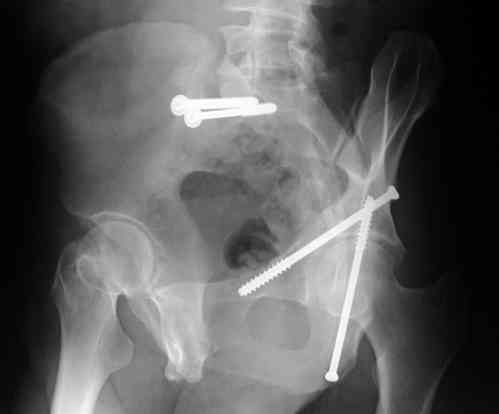

I'll include a few images of a similar injury in a similarly large male patient. This patient "showed up" in our ER c/o hip pain 2 months after being treated in the lateral position, without a quality reduction, without an anterior column transverse supporting implant, with an unbalanced plate applied too medially, with insufficient caudal segment fixation...it took over 8 hours and a 3+ l blood loss to debride the callus from front then

back, excise the HO, release his sciatic nerve, reduce the head-transverse-wall, and fix it...and now it's a staging procedure.

The 2nd example is of a motorcyclist with a transverse fracture-dislocation...he had a closed attempted reduction and placed in traction but the manipulative reduction was not concentric (not unusual for this injury pattern)...so the traction was adjusted to be just enough to disengage the head from the fracture (12#) until he could be cleared for surgery one day after injury...he was treated "urgently" then with a prone KL, clean the fracture, reduce and clamp it, screw it, support with a balanced plate, close, and enjoy...2-3hours, 400cc EBL, blah, blah, blah..